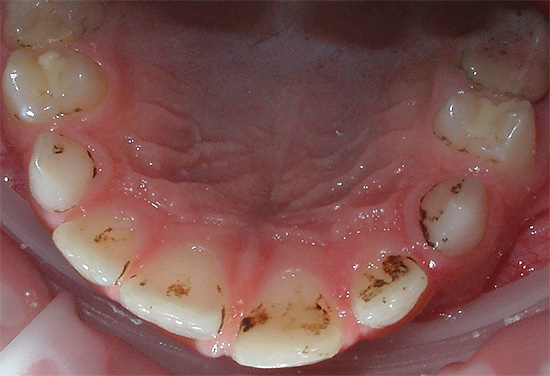

- Una diminuzione della concentrazione di calcio e composti del fluoro sia nella saliva che nel sangue a causa di un certo consumo per le esigenze di un embrione in via di sviluppo. Allo stesso tempo, il calcio non viene consumato dai denti stessi, come molti credono in modo errato. Ma la rimineralizzazione dello smalto e il suo rafforzamento, che si verificano sempre in altri periodi a causa dell'azione della saliva, durante la gravidanza possono rallentare o addirittura arrestarsi. Di conseguenza, lo smalto diventa debolmente mineralizzato e viene più facilmente danneggiato dai rifiuti acidi prodotti dai batteri.

- Cambiamenti ormonali nel corpo e, di nuovo, i corrispondenti cambiamenti nella composizione della saliva, che porta a una diminuzione delle sue proprietà battericide. In poche parole, la saliva delle donne in gravidanza in alcuni casi è meno efficace nell'uccidere i batteri cariogeni.

- Disturbi della cura dentale - a causa di affaticamento, tossicosi, preoccupazioni e confusione, alcune donne incinte dimenticano regolarmente di lavarsi i denti o non lo fanno completamente.

- Rispetto delle regole di igiene orale: i denti vengono lavati dopo ogni pasto, preferibilmente con paste selezionate dal dentista; dopo atti casuali di vomito con tossicosi, la bocca viene sciacquata con una soluzione di soda per neutralizzare gli acidi dal vomito.